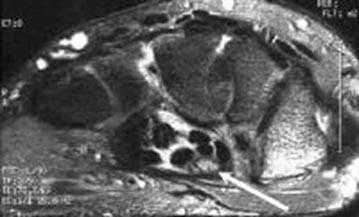

Клинически: Острая боль. В анамнезе нет травмы или чрезмерной нагрузки. Увеличение диаметра и повышение МР-сигнала в проекции сухожилия разгибателя.

Синдром повреждения сухожилий включают частичные и полные их разрывы, проявления теносиновита и посттравматического тендиноза. Основную долю составляют теносиновиты, возникающие изолированно или на фоне повреждения костей и связок. Морфологически теносиновиты характеризуются скоплением синовиальной жидкости под оболочками сухожилия. Рентгенодиагностика в диагностике теносиновитов неинформативна. Наиболее информативны в диагностике теносиновита УЗИ и МРТ.

Теносиновит сухожилий глубокого сгибателя пальцев кисти и длинного сгибателя большого пальца.